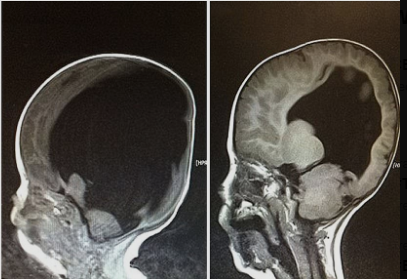

In 2012, Noah Wall entered the world facing seemingly insurmountable odds. Born with just 2% of his brain, he carried the burdens of Spina Bifida and hydrocephalus – conditions that result in a fluid build-up on the brain. The prognosis was grim, and medical experts predicted he wouldn’t survive birth. His mother, Shelly, faced the challenging decision of whether to terminate her pregnancy – advice she received on five separate occasions.

Noah’s early years were marked by doctors’ dire predictions – he was not supposed to walk, talk, or even eat unaided. Yet, Noah proved to be a living example to the resilience of the human spirit. By the age of three, he had defied the odds and regained a remarkable 80% of his brain.